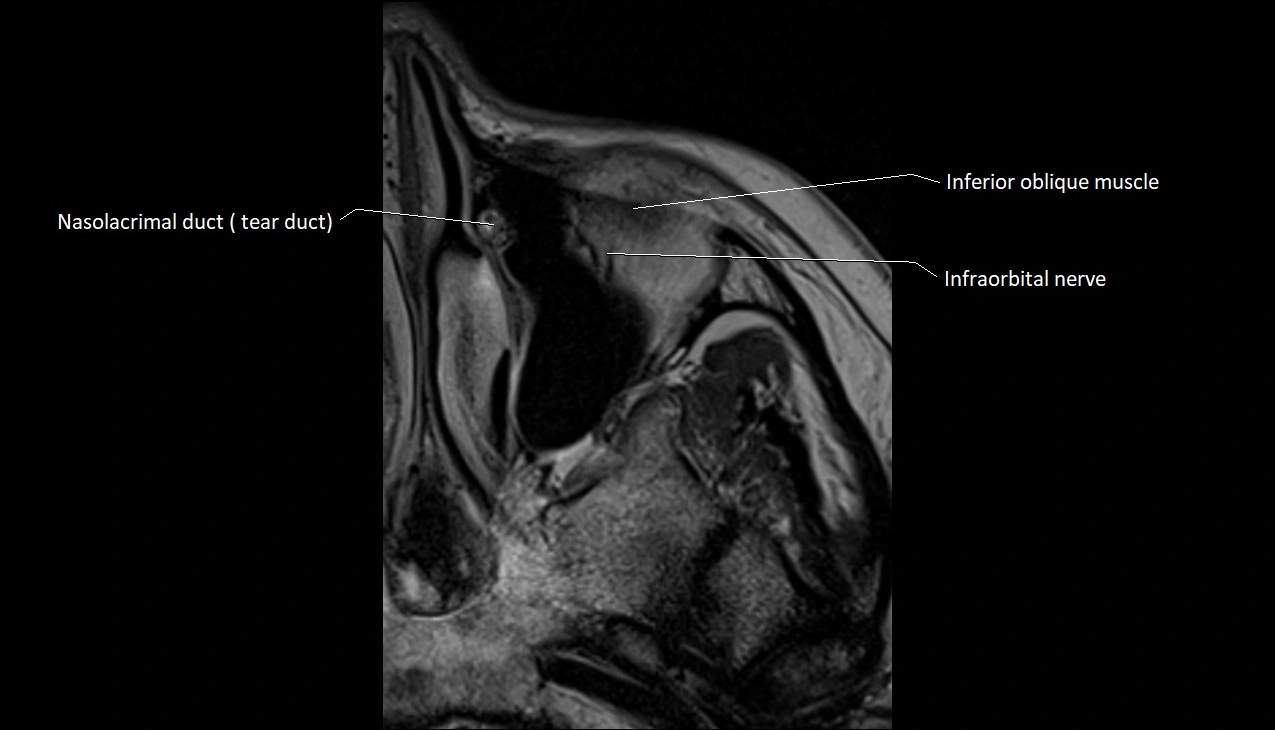

- Nasolacrimal duct (Tear duct)

- Inferior oblique muscle

- Infraorbital nerve